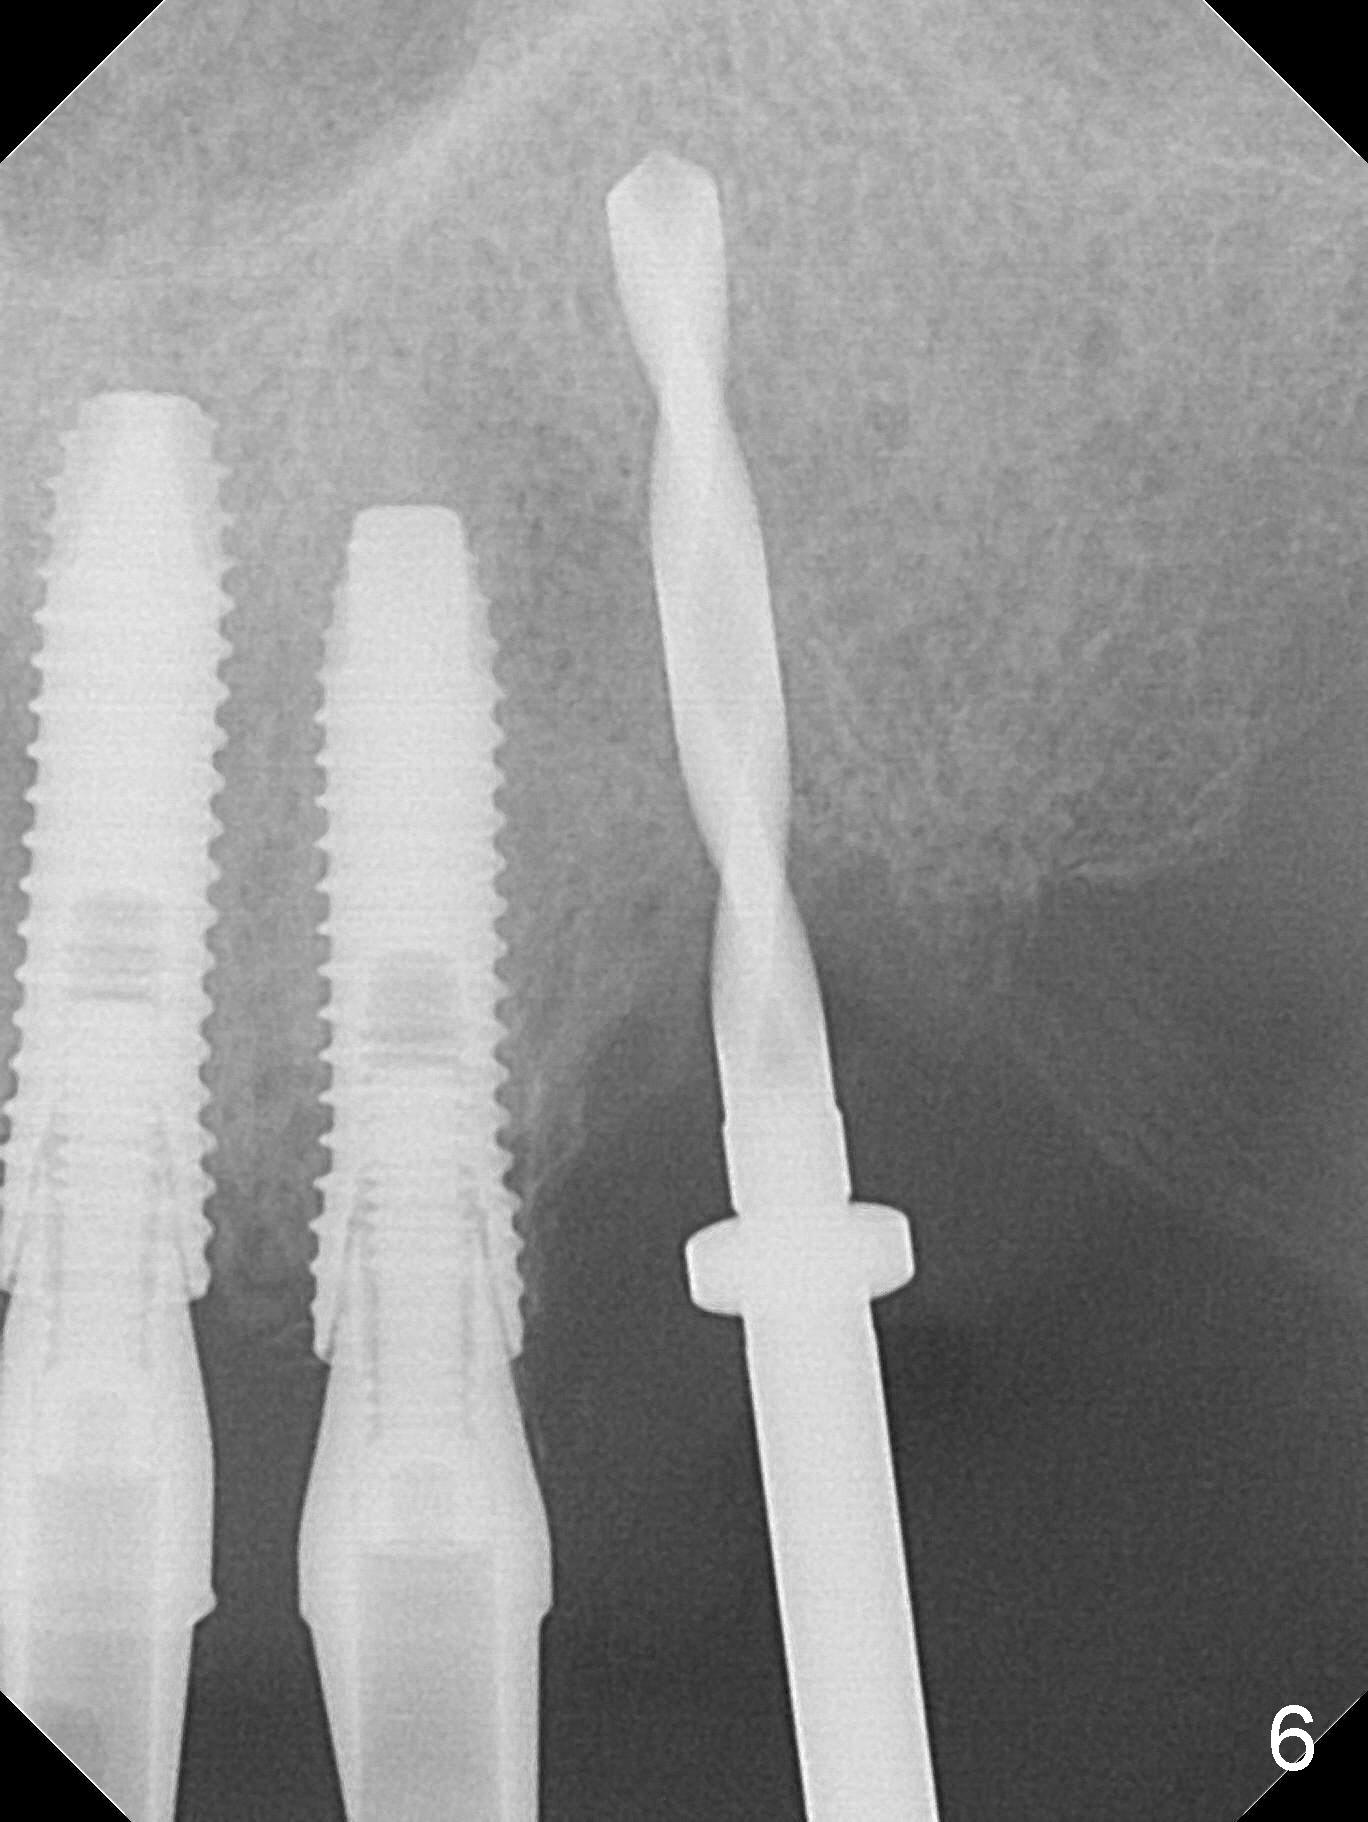

The dentition is poor except #6 and 8 (Fig.1). The gingiva is erythematous at #9-11 (Fig.2). The teeth #9 and 10 are extracted first; a 4x16 mm UF implant is placed at #9, while a 2 mm pilot drill is at the site of #10 (Fig.3). The implant at #9 is placed deeper with placement of 4.5x5.5(5) mm abutment; a 3.8x15 mm implant is placed at #10 initially (Fig.4). While the latter is placed deeper, a 4x16 mm implant is placed at #11 (Fig.5 after removal of #11-15 FPD (fixed partial denture)). In fact the trajectory at #11 is not difficult to be changed with 2 mm drill (Fig.6). After use of 3 mm drill, the implant is reinserted at #11 with ideal trajectory (Fig.7). After further seating of the implant at #11, graft is placed in the remaining sockets of #9-11 (Fig.8 *; later more graft is placed mesial to #11 implant (^)). Finally, a 4.5x7(5), 4.5x15° B (4) and 5.5x7(5) mm abutments are tightened and prepared (Fig.9) for splinted provisional at #9-10.